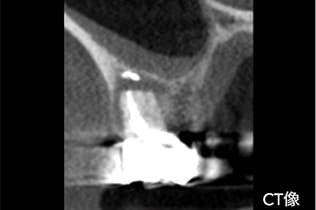

Case04

-

- 原因

- 歯根嚢胞

- 治療内容

- 歯根端切除法

- 治療費用

- ¥110,000

他院で治療した歯が腫れていて、様子を見るように言われたが、なかなか治らない、とのことでご来院された患者さんです。歯根端切除術を行い、腫れもなくなり、経過良好です。

<リスク・副作用>

外科手術のため、術後に出血、痛みや腫れ、違和感を伴います。口腔内の状態によっては適応できないことがあります。歯根端切除で治らなければ抜歯を検討しなくていけない場合もあります。